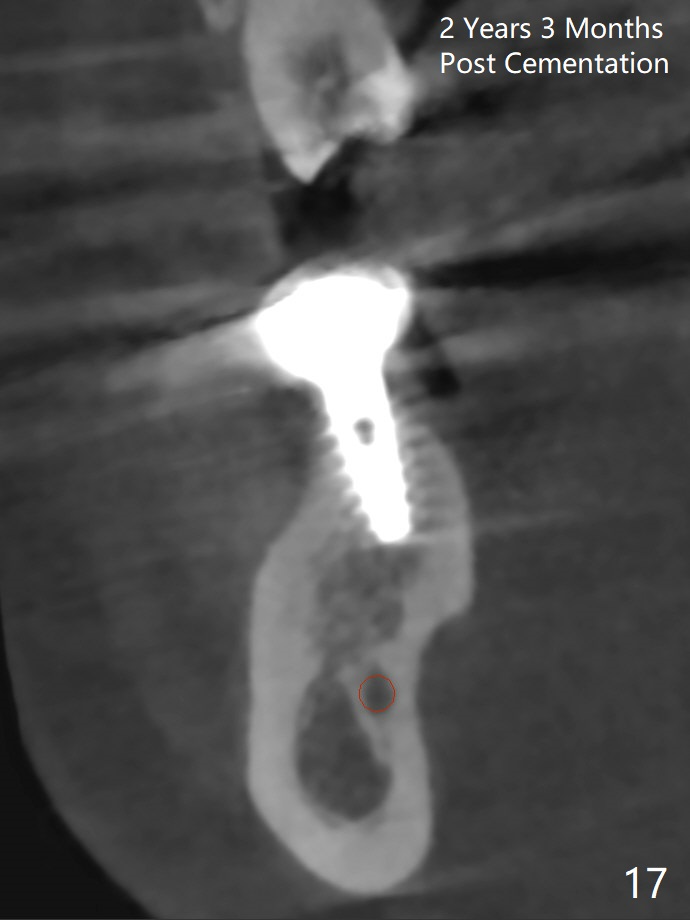

CBCT was taken (Fig.1,2 (P: pontic; S; submandibular fossa)) several months prior to #29 and 31 RCT and #31 porcelain chip (Fig.3). When the bridge is sectioned, the pointed ridge at #30 (Fig.1 >) is confirmed (Fig.4,5). After flattening the ridge until the ridge is 6 mm wide buccolingually (Fig.6 arrowheads), osteotomy is initiated with 1.6 mm drill at 9 mm; there is 2.5 mm clearance from the superior border of the Inferior Alveolar Canal (red dashed line). A 4.5x9(1) mm Magicore is placed with 35 Ncm (insertion torque) after 4.3 mm Magic Drill; a 4.5 mm healing abutment (Fig.7 H). An error occurs because of using 1 mm cuff of the Magicore. Ideally 3 or 4 mm cuff should have been used because of reduction in the ridge by ~ 3 mm. She returns because of failure of 18-20 bridge (implants will be placed at 18/19). The implant at #30 is in fact not placed deep enough; the coronal threads seem to be exposed, although there is no periimplantitis (good oral hygiene, Fig.17).